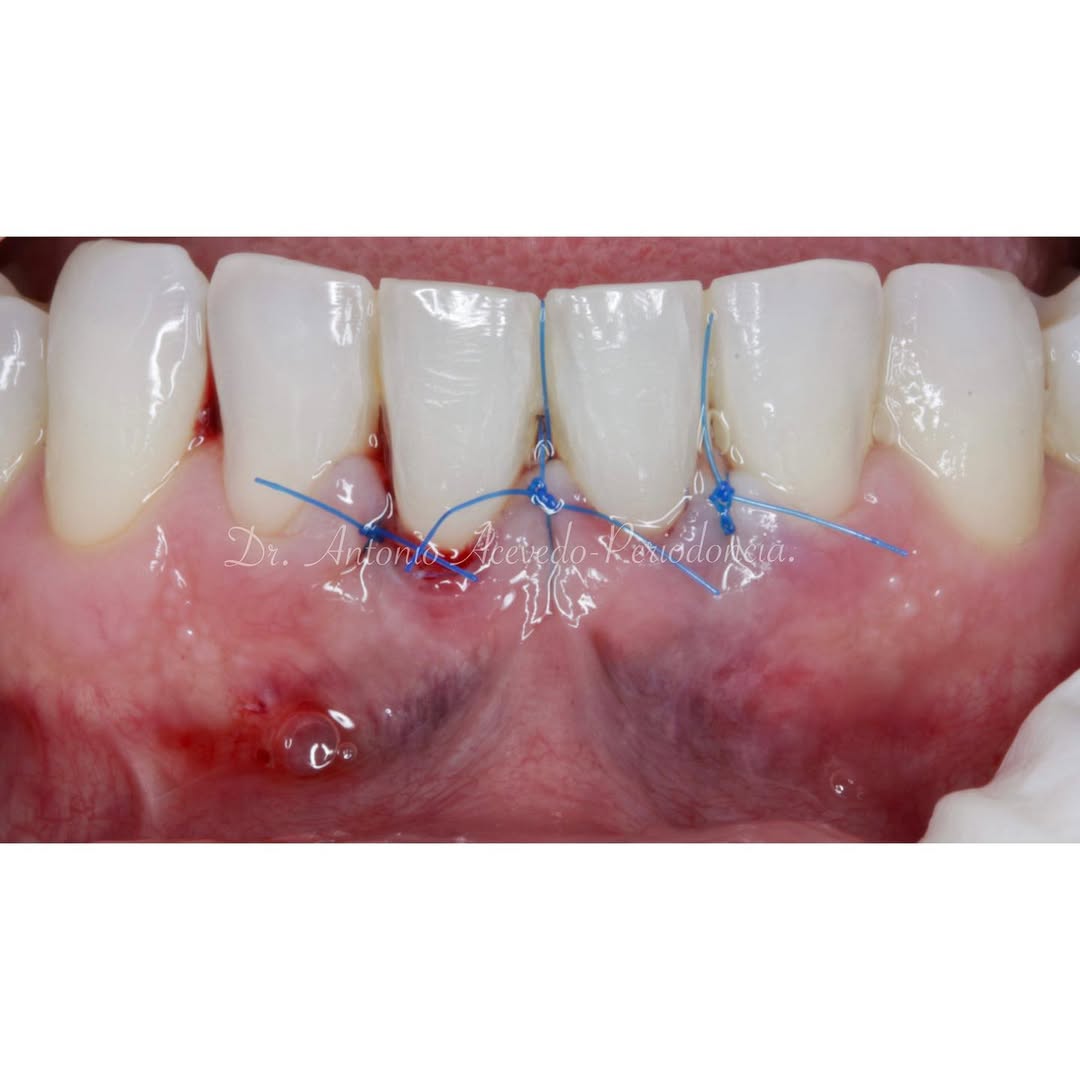

Durante una mañana, asistirás a una Cirugía Mucogingival de recubrimiento radicular de recesiones múltiples en IV y V sextante (36 a 43).

Gracias al uso del microscopio y a la proyección en tiempo real en pantalla, verás exactamente lo mismo que veo yo durante la cirugía, sin tener que estar

Aprende la planificación y técnica de la cirugía Mucogingival para el recubrimiento de recesiones y aumento de banda queratinizada en el sector anteroinferior

Durante una mañana, asistirás a una Cirugía Mucogingival de recubrimiento radicular de una recesión unitaria en 31 con frenillo asociado. Gracias al uso del microscopio y a la proyección en tiempo real en pantalla, verás exactamente lo mismo que veo yo durante la cirugía, sin tener que estar